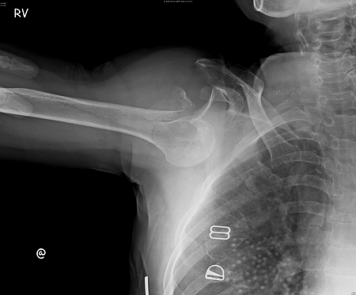

22 56 歲女性,走路散步不慎向後跌倒,手部撐地並肩部著地損傷,肩部疼痛、腫脹,呈「方肩」畸形, 肩外展活動受限,肩關節照 X 光片(如圖示),其診斷為下列何者? (A)僅肩關節脫臼 (B)僅肱骨外科頸骨折 (C)肩關節脫臼合併肱骨大結節骨折 (D)僅肩關節周圍炎